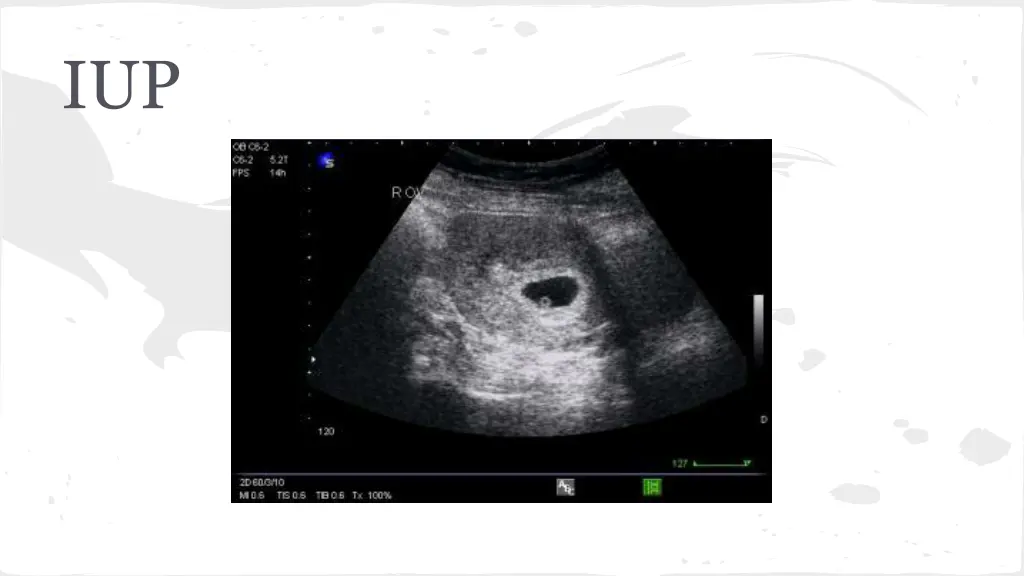

Ectopic Pregnancy-Likelihood Ratios CMT-4.9 Adnexal mass-2.4 Adnexal tenderness 1.9 Ultrasound-111 No IUP on US in pregant patient is ectopic until proven otherwise

Ectopic Pregnancy Symptoms Abdominal Pain Syncope Vaginal Bleeding Vomiting Exam Lower abdominal tenderness Adnexal TTP CMT Peritoneal Abdomen

Ectopic Pregnancy Labs Quant B-HCG, CBC, Coags, Type and Screen -very low B-HCG cannot rule out ectopic Management -STAT GYN consult -NPO -Medical vs Surgical Management